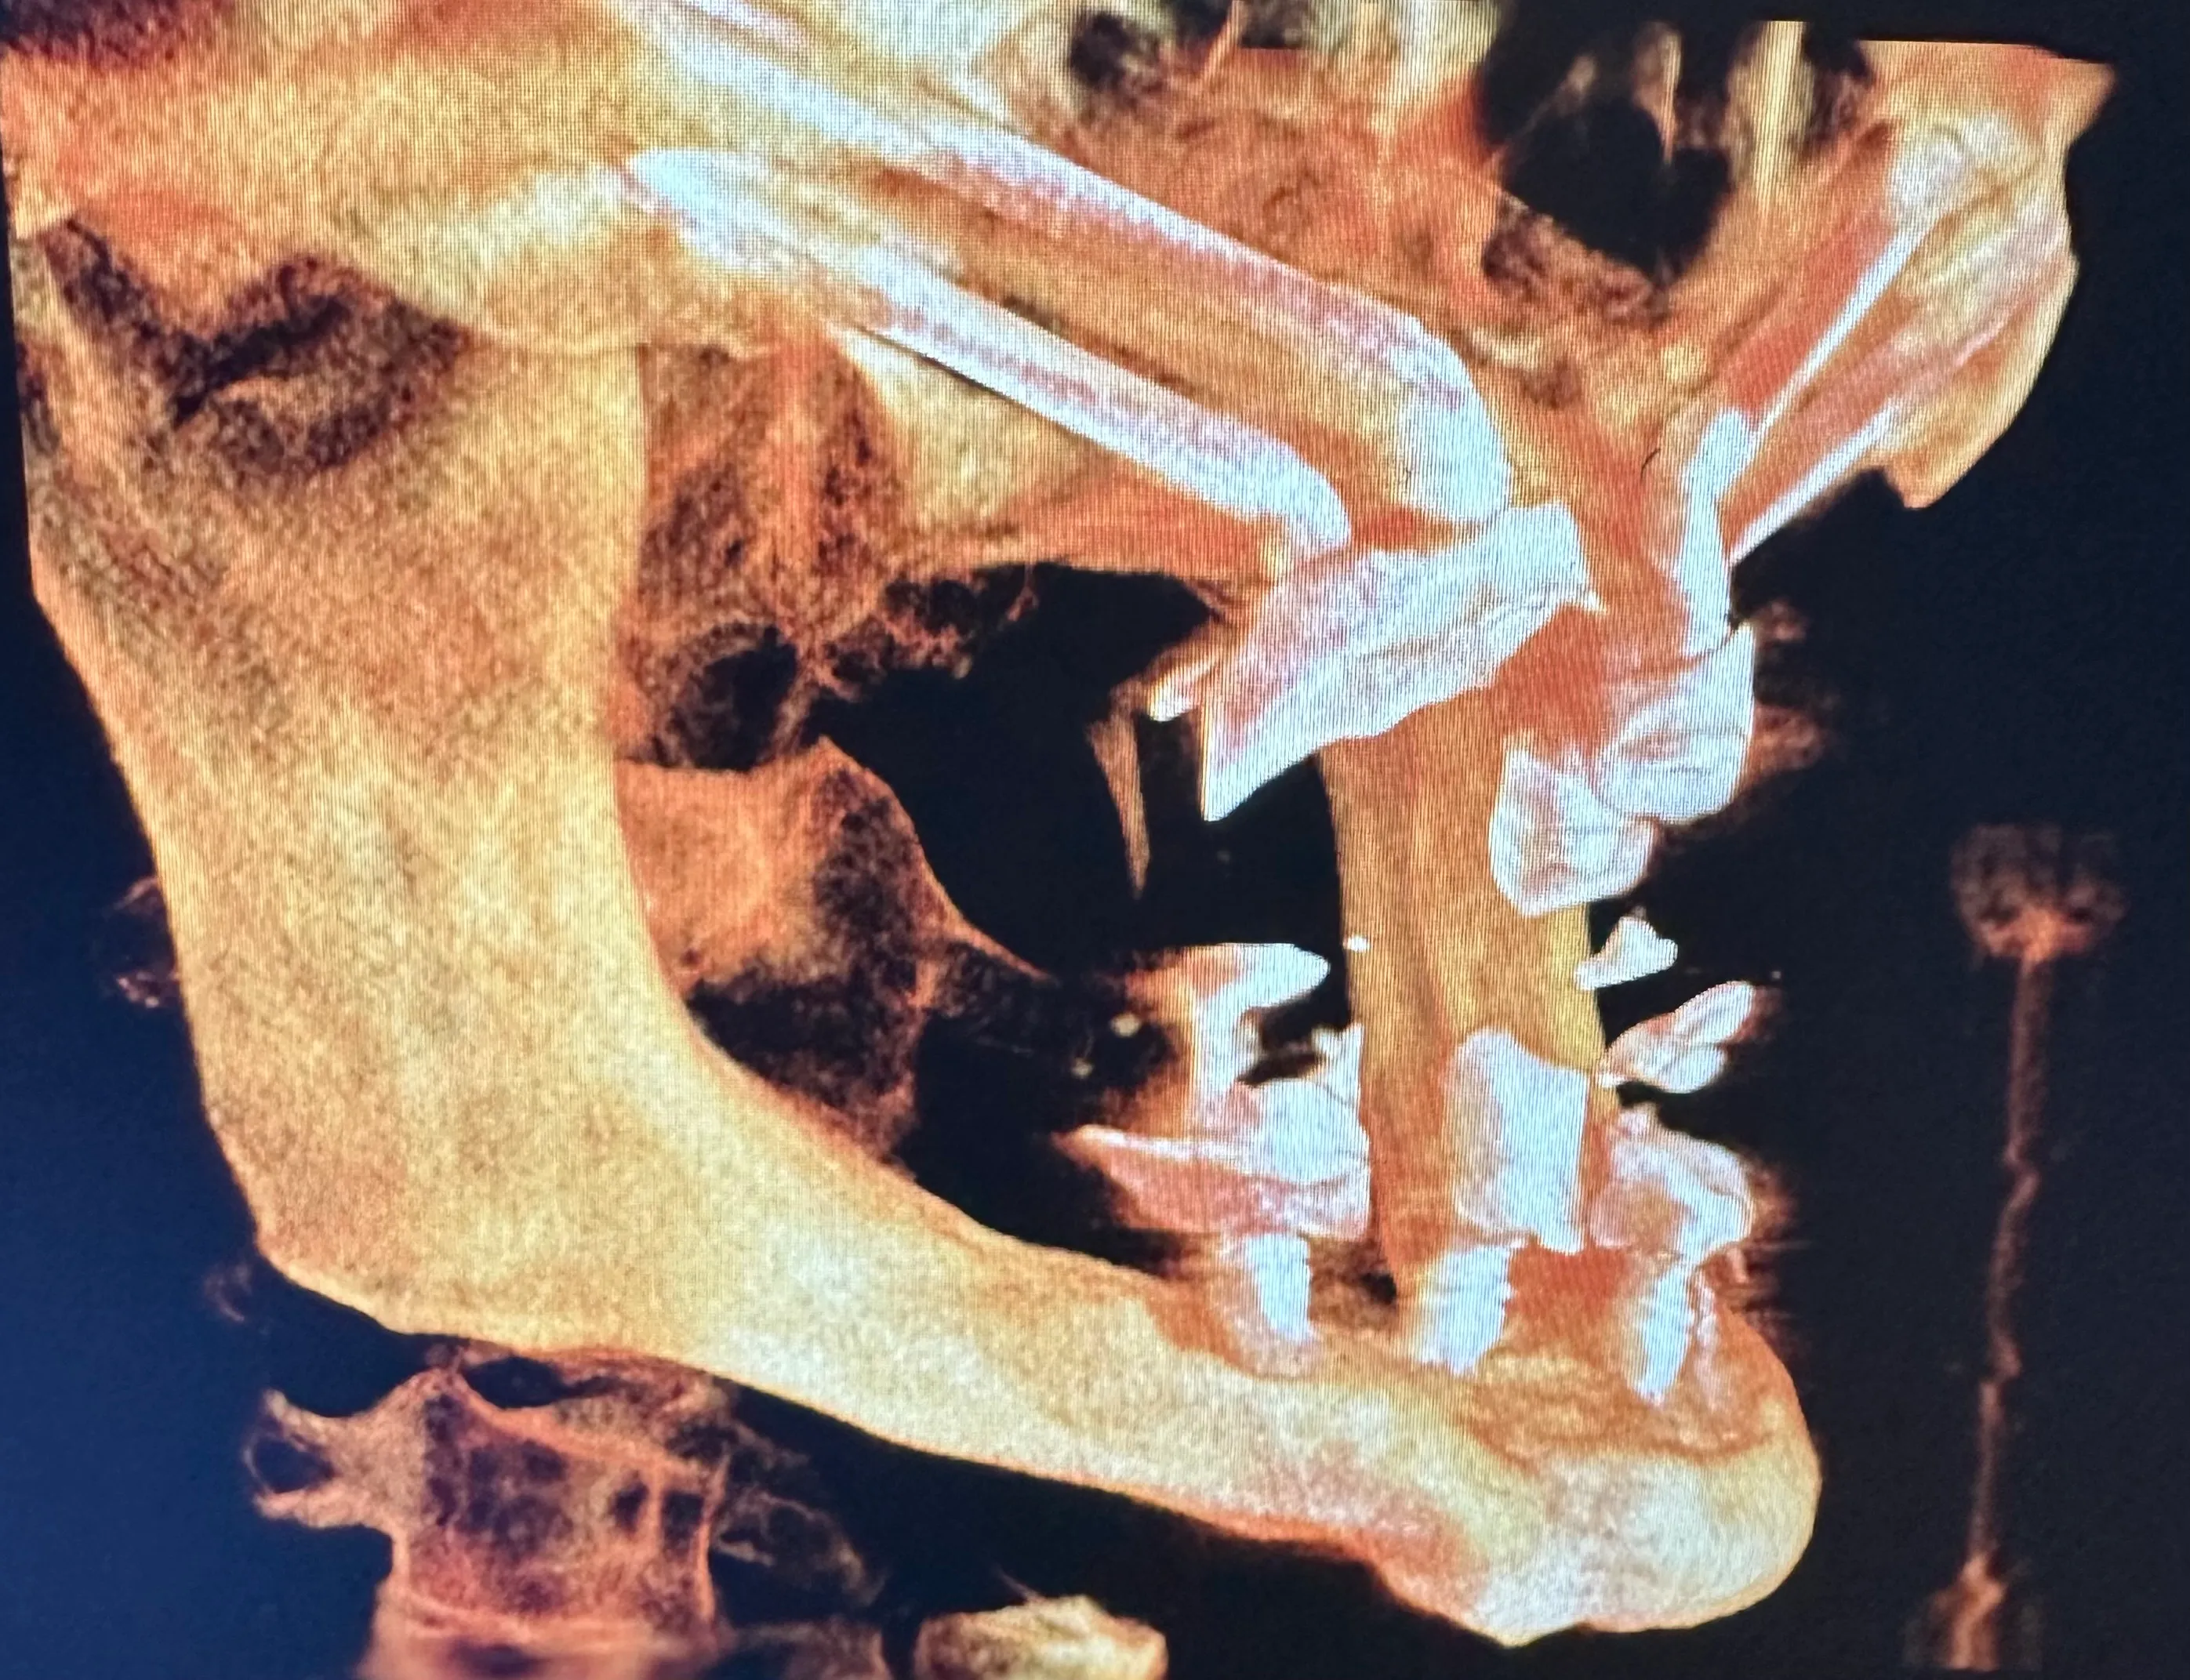

X-ray image of a jaw with dental implants and surgical plates, highlighting the alignment of teeth and orthopedic hardware.

Normally, implants are placed in the maxilla to replace missing teeth in the upper jaw. However, some patients have such severe bone loss that there isn’t enough to place an implant safely. In this case, longer implant screws can be used to reach the cheekbones, which are used as an anchor instead.

Zygomatic dental implants are sometimes called “rescue implants” because they can help patients achieve a fully functional bite and aesthetically pleasing smile when bone grafting isn’t possible.